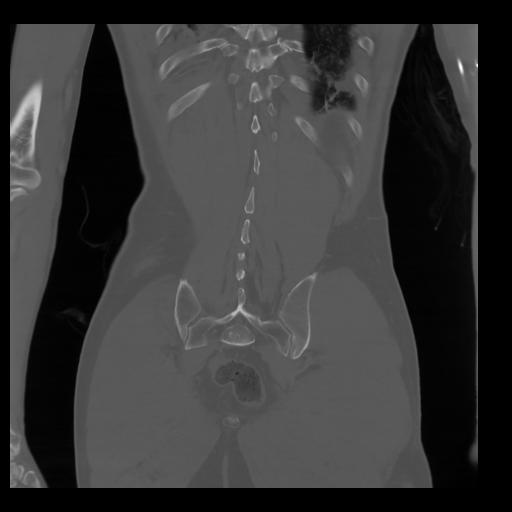

35 CUERPO,CE,Coronal,3.000,CUERPO,Coronal,